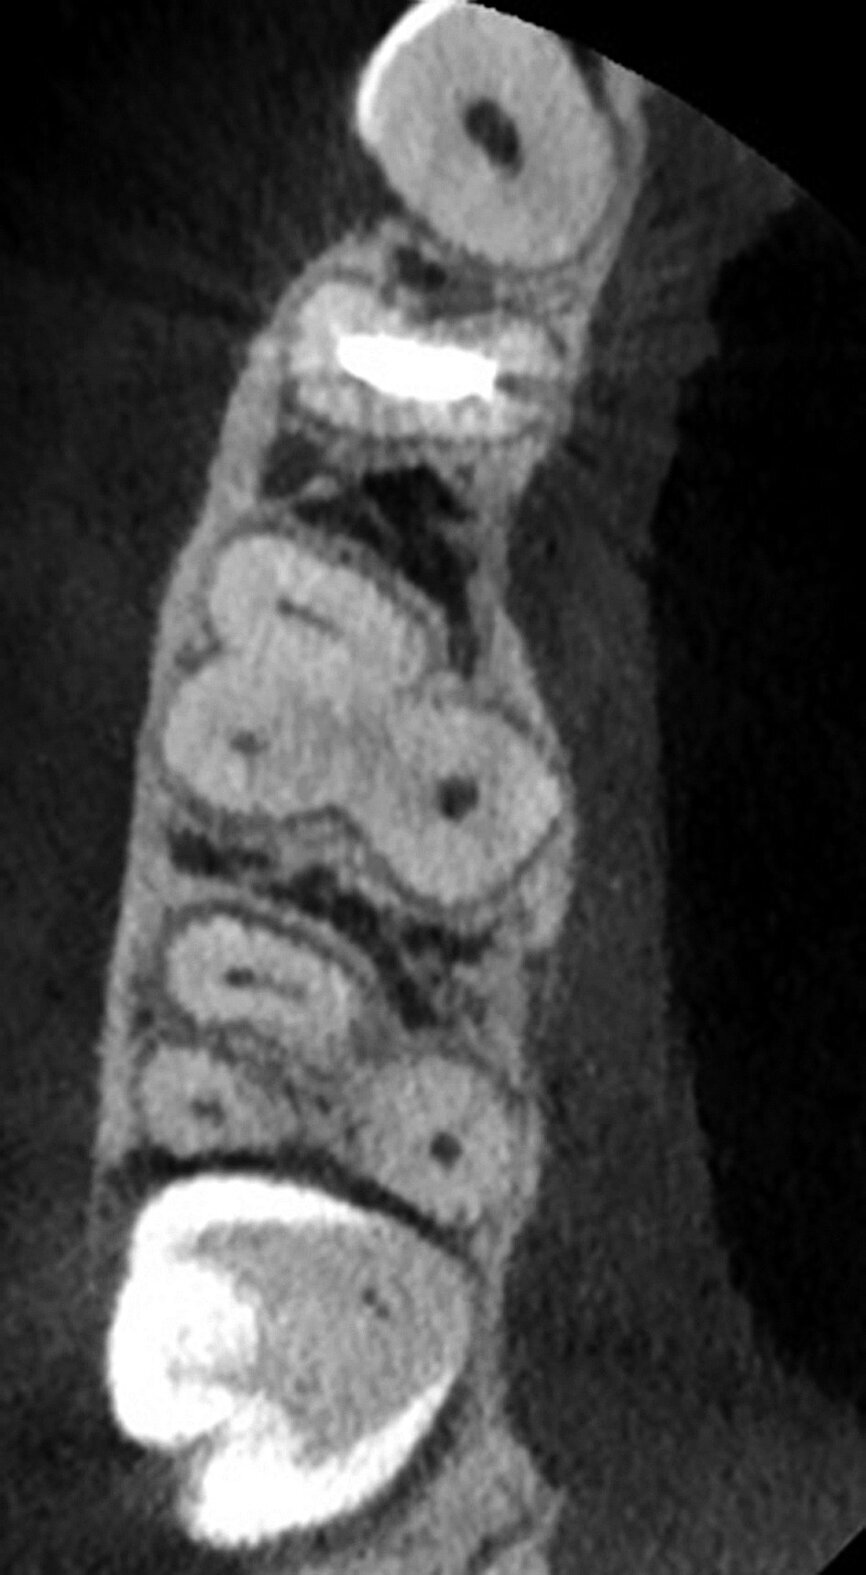

The patient, a 25-year-old female, reported with irreversible pulpitis on her maxillary second left molar. The tooth was temporarily restored with Intermediate Restorative Material (IRM, Dentsply Sirona) and the patient complained about continuous food impaction between her maxillary left, first and second molar teeth (Fig. 2). A periapical radiograph revealed that the temporary restoration was not sealing at the gingival margin (Fig. 3). Also, visible on the periapical radiograph was evidence of possible curvatures in the mesiobuccal and distobuccal roots. It was decided, with the consent of the patient, to take a limited field of view CBCT scan to explore the anatomy of this tooth. The CBCT scan revealed the presence of three root canal systems when viewed in the axial plane; and in the sagittal plane, evidence of severe root curvatures were present in the mesiobuccal and distobuccal root canal systems. It was decided to do a more in-depth investigation as a result of this complex anatomy, using the 3D Endo Software (Dentsply Sirona).

The second step, ‘3D Tooth Anatomy’, involved selecting the tooth to be examined and the entire volume was cropped to only leave the data of interest behind (Fig. 5). In the third step, ‘Canal System’, the number of root canals were identified and each root canal was then mapped separately by identifying the orifice and radiographic apical foramen of each root canal (Fig. 6).

With the fourth step, ‘3D Canal Anatomy’, the software made a proposal of the canal anatomy (Fig. 7), but the operator can make corrections according to the canal configuration that can be viewed in different planes in the software. Figures 8 to 10 show the mapping of the palatal, mesiobuccal, and distobuccal root canal systems.